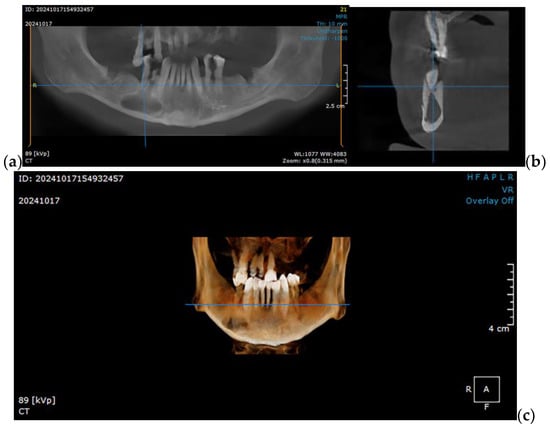

2.1. Optimizing the Mandibular Model for Simulation

2.2. Post Tumor Ablation Defect Simulation